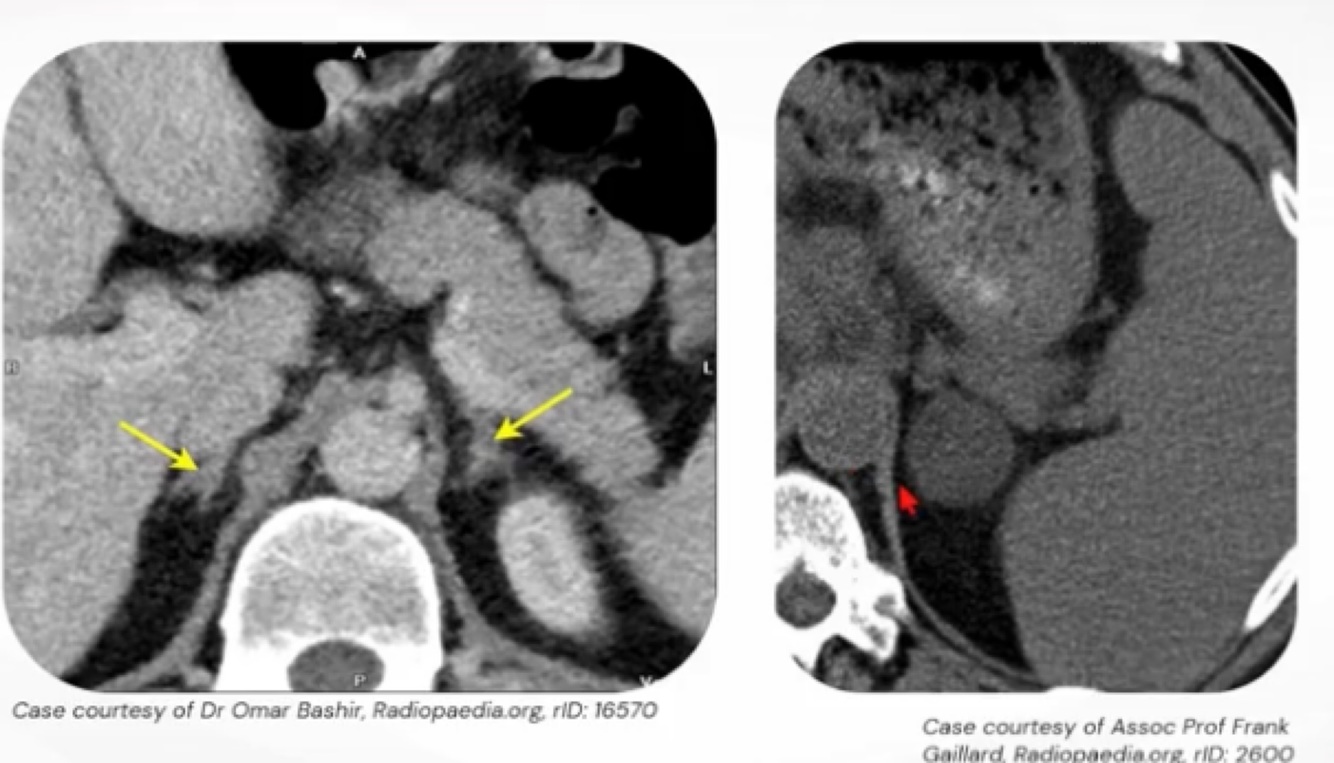

3

Q

Achados nas imagens:

A

Imagem da esquerda: adrenais normais, imagem da direita: nódulo de adrenal.